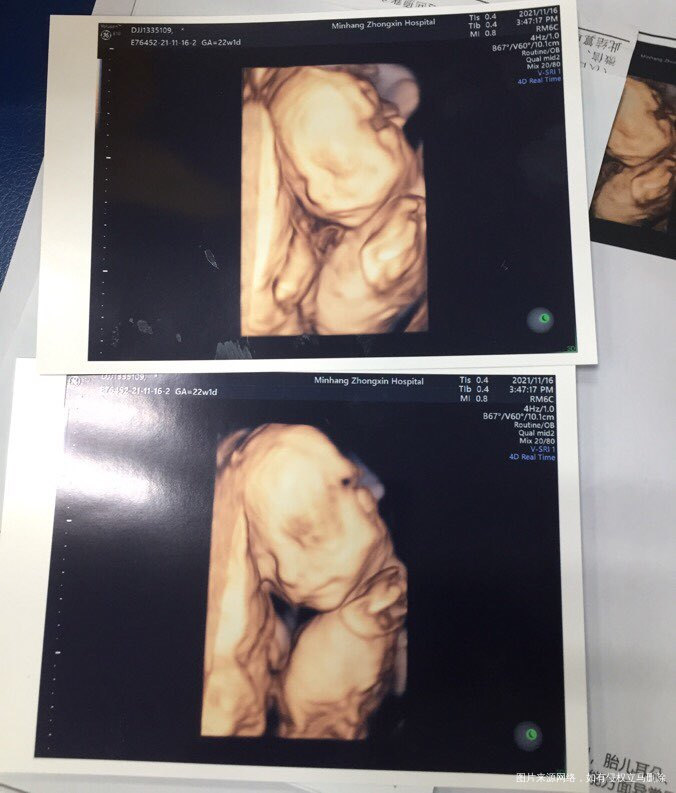

做4维折腾了一下午,娃不太配合,一直动来动去的,做了2遍,好在最后还是通过了[大笑][大笑][大笑]